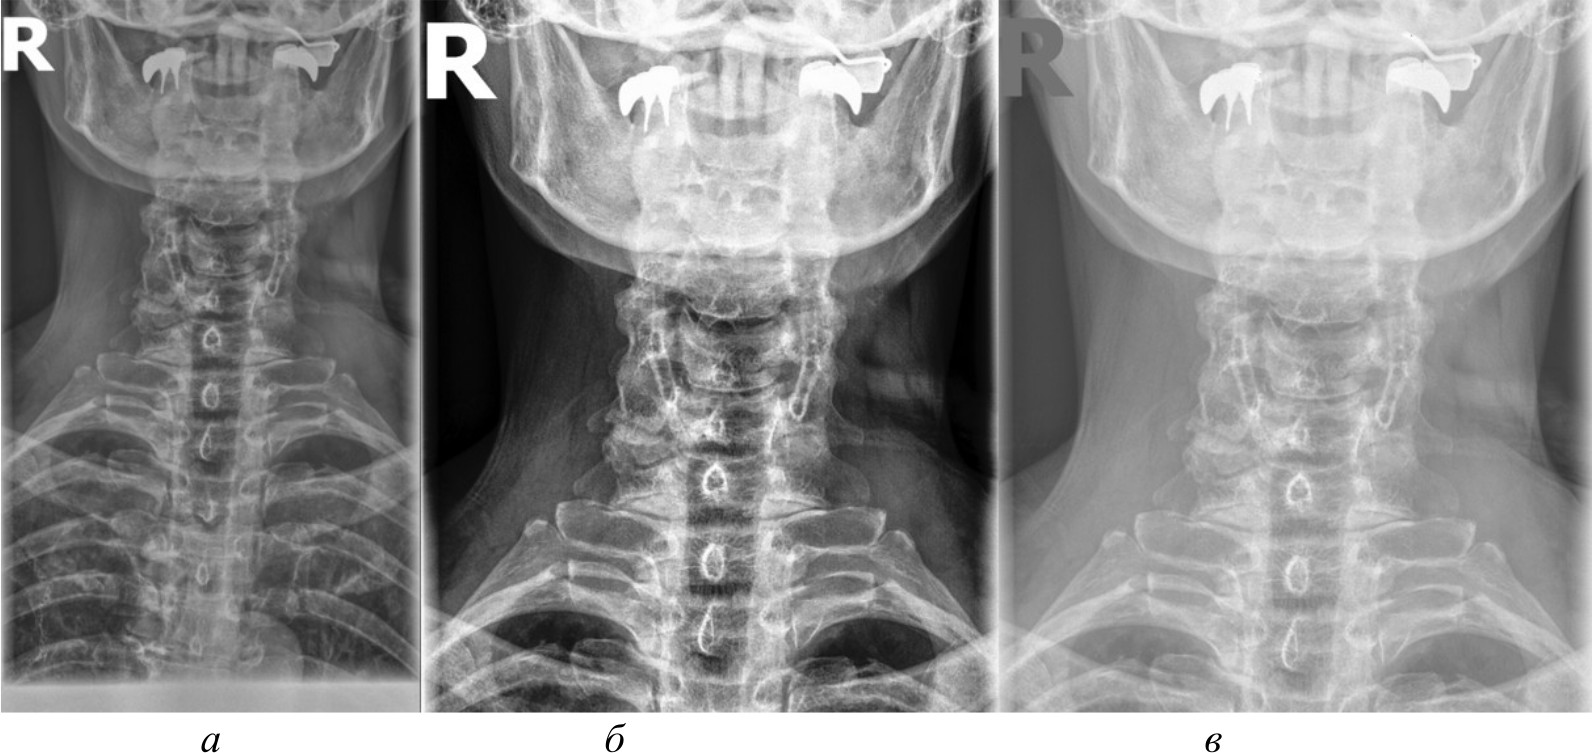

Для создания эталонного набора изображений рентгеновские снимки в формате DICOM были загружены в специализированное программное обеспечение для медицинской визуализации. DICOM является стандартным форматом для медицинских изображений, который позволяет сохранять изображение с высоким качеством и дополнительной информацией об исследовании. Однако для дальнейшей обработки и анализа эти DICOM-файлы конвертируются в более распространенные графические форматы. Специализированное программное обеспечение сохраняет их в формате PNG. На рис. 2, а представлено изображение, полученное в результате работы в специализированном программном обеспечении.

Для сравнительного анализа использовались различные методы и алгоритмы компьютерного зрения. Помимо изображений в формате PNG, конвертированных из исходных DICOM-файлов, применялись и другие подходы, направленные на извлечение более качественных изображений непосредственно из DICOM-данных, среди которых:

- базовое отображение Python. Изображения загружены в Python и отображены при помощи библиотеки Pillow без применения каких-либо дополнительных преобразований. Данный метод представлен на рис. 2, б;

- медианный фильтр. Для сглаживания шумов и артефактов на изображениях к базовому отображению Python применен медианный фильтр из библиотеки OpenCV. Размер окна фильтра был подобран эмпирически. Данный метод обработки представлен на рис. 2, в;

- адаптивная эквализация гистограммы. Для улучшения локального контраста изображений помимо базового отображения Python использована адаптивная эквализация гистограммы из библиотеки OpenCV. Метод адаптивной эквализации представлен на рис. 3, a;

- стандартная эквализация гистограммы. Для сравнения с адаптивной эквализацией помимо базового отображения Python применена стандартная эквализация гистограммы из OpenCV. Данный метод представлен на рис. 3, б;

- гамма-коррекция. Для регулирования яркости и контрастности изображений, а также для сравнения с двумя предыдущими эквализациями использована гамма-коррекция. Значение гамма-параметра подбиралось эмпирически. Гамма-коррекция представлена на рис. 3, в.

Рис. 2. Изображение, полученное при помощи специализированного программного обеспечения (а), метод базового отображения в Python (б), метод базового отображения Python с применением медианного фильтра (в)

Исходя из полученных изображений при использовании различных методов можно сделать следующие выводы:

- базовое отображение DICOM-данных с помощью библиотеки Pillow показало наличие значительного количества шумов и размытых объектов на полученных изображениях, что затрудняет четкое обнаружение анатомических ориентиров;

- применение медианного фильтра для сглаживания артефактов привело к чрезмерному размытию деталей на изображениях, сделав их еще менее пригодными для дальнейшего анализа;

- использование методов эквализации гистограммы продемонстрировало значительное улучшение контрастности и четкости визуализации анатомических структур по сравнению с базовым отображением и медианной фильтрацией;

- гамма-коррекция изображений, в отличие от эквализации, больше повлияла на яркость, нежели на контрастность, поэтому показала себя хуже в контексте задачи выделения ключевых анатомических ориентиров;

- отображение изображений в формате PNG, полученных из исходных DICOM-данных после применения ряда предварительных обработок с помощью специализированного программного обеспечения, продемонстрировало качество визуализации несколько меньшее, чем у методов эквализации, но при этом превосходящее качество других рассматриваемых методов обработки. В итоге комплекс предварительных обработок, необходимых для конвертации DICOM-данных в формат PNG, позволяет достичь качества визуализации, которое хотя и уступает эквализации, но превосходит другие методы.

Рис. 3. Метод адаптивной эквализации гистограммы, метод стандартной эквализации гистограммы, метод гамма-коррекции